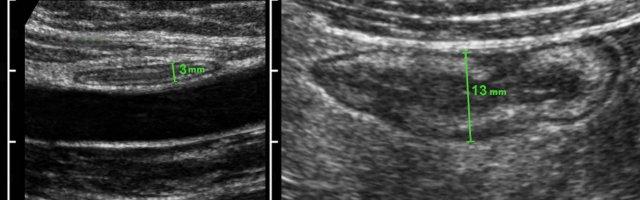

Đo độ dày thành ruột được thực hiện tốt nhất và có tính tái lập cao nhất trong khi ép, như ở đây trên một người bình thường (bên trái) và ở một bệnh nhân mắc bệnh Crohn (bên phải).

Các phép đo được thực hiện từ bờ ngoài của lớp cơ đến phía đối diện, sau đó chia cho 2, cho kết quả độ dày thành lần lượt là 1,5 mm và 6,5 mm đối với hồi tràng bình thường và hồi tràng Crohn.